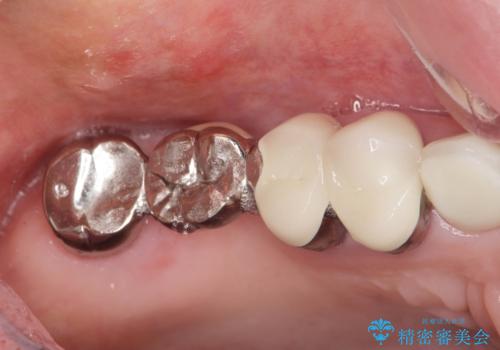

- 数年前にいれた右上のブリッジが、「ぐらついて痛い、噛めない。」と改善を希望され来院されました。

X線写真より、咬合力負担能力に十分で無い親知らずを使用した長いブリッジが装着されており、力の負担に耐え切れずぐらつきが増加してきた状態です。

親知らず、ブリッジを抜去・撤去しインプラントを用いた咬合機能回復を行っていくこととしました。